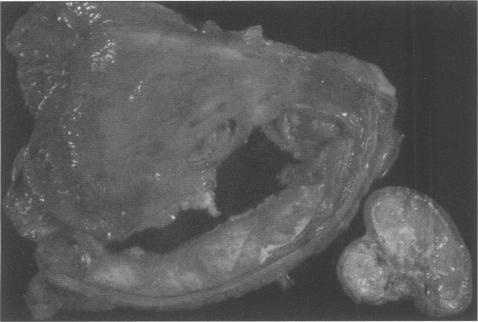

A 9-year-old, quarter horse gelding with obstructive urethrolithiasis was treated with a perineal urethrostomy. The horse's condition deteriorated and abdominocentesis confirmed septic uroperitonitis. The horse was euthanized and postmortem examination revealed peritonitis, a tear in the lateral wall of the bladder, and a nephrolith within the left renal pelvis.

一匹9岁的夸特马种公马患有阻塞性尿道结石,接受了会阴尿道造口术治疗。该马的病情恶化,腹腔穿刺证实为感染性尿性腹膜炎。对该马实施了安乐死,尸检发现有腹膜炎、膀胱侧壁撕裂以及左肾盂内有一枚肾结石。